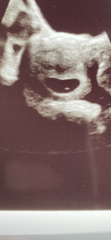

@Moominmiss @Juno231thank you both so much. I saw my baby bean 🥰. First thing I noticed was the super strong heartbeat. Measuring 6wks and 6days so only two days behind what I thought. Bean is 1cm big!! Crazy!

Tracking your cycle and possible BFP using RHR - part 5

@mumof23188 omg they’re amazing photos!!